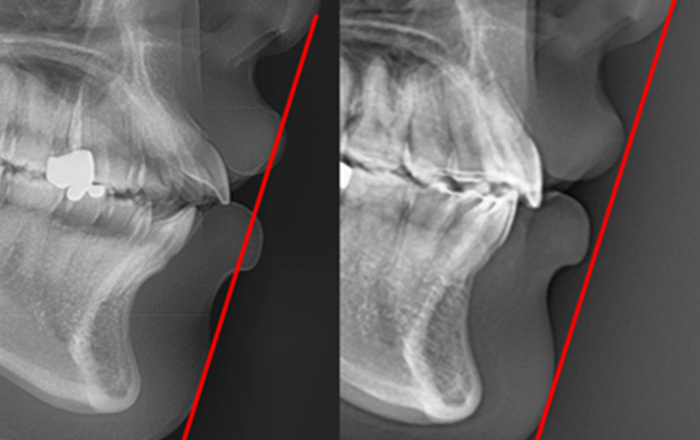

Cephalometric X-ray 촬영

2~3초의 짧은 시간 안에

얼굴의 측면 엑스레이 촬영이 가능합니다. -